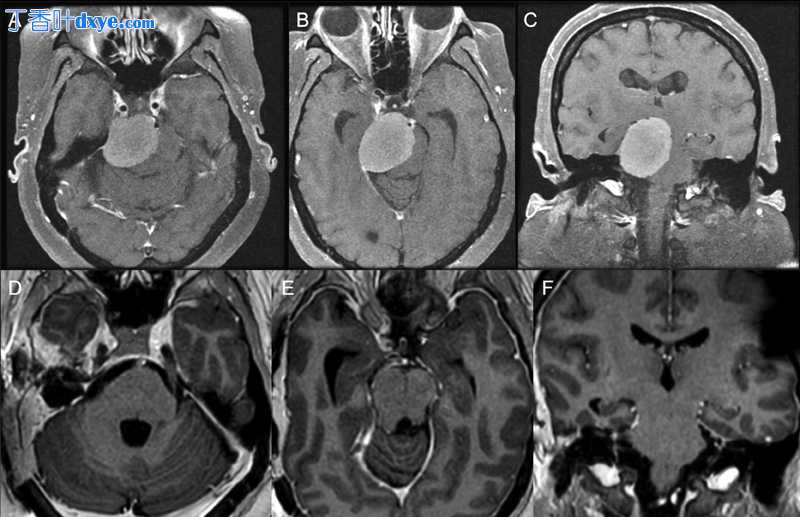

岩斜脑膜瘤位于颅底深处,邻近重要的神经血管结构,是一种难以对付的病变。岩骨联合入路包括岩骨前部切除术和迷路后岩骨后部切除术,允许岩斜区肿瘤在幕上和幕下暴露,同时可能保留听力功能(图1)。在这份手术视频图谱手稿中,作者展示了一种通过岩骨联合入路显微手术切除岩斜脑膜瘤的分步技术。显微外科和颅底技术的细微差别包括岩骨钻孔、天幕横切、肿瘤切除和硬膜缺损的多层重建。岩骨联合入路允许多个迎角,包括颞下和乙状窦前走廊。总之,岩骨联合入路加内镜辅助是岩斜脑膜瘤手术切除器械中的一项重要策略(图2)。

图 1 (A, B) 术前钆后 T1 加权轴位 (A 和 B) 和冠状位 (C) MRI 显示右侧岩斜脑膜瘤伴严重脑干受压和脑积水。 (D, E) 术后 3 个月钆后 T1 加权轴位 (D 和 E) 和冠状位 (F) MRI 显示肿瘤大体全切除成功,脑干减压和再扩张。 脑积水通过脑室腹腔分流术解决。 核磁共振,磁共振成像。